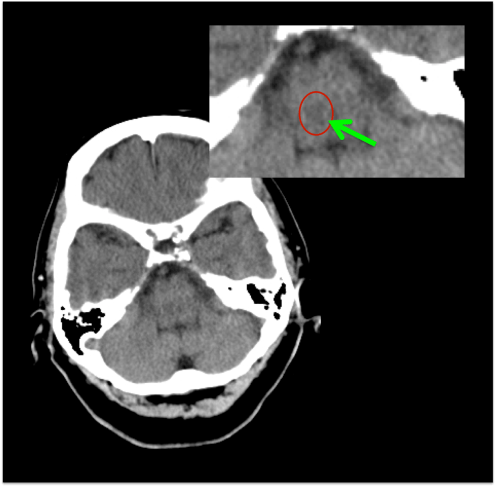

FRACTURAS DE CRÁNEO.

Con ventana de hueso.

Las reconstrucciones 3D-VR aumentan la capacidad diagnóstica de las fracturas desplazadas y no desplazadas.

La presencia de fractura no se correlaciona con la severidad del daño cerebral, sin embargo, la incidencia de hemorragia intracraneal es mayor en pacientes con fractura que en los que no la presentan. Al mismo tiempo, el 25% aprox. de pacientes con daños cerebrales fatales no muestran fractura de cráneo.

- Fracturas lineales = las más frec. -> baja incidencia de daño cerebral.

- Fracturas con hundimiento -> asocia contusiones y roturas durales.

- Fracturas de la base -> pueden ser transversas o diagonales, éstas con mayor índice de mortalidad. Pueden causar ceguera, afectación de pares craneales, pédida de audición, fuja de LCR. En las fracturas que afectan al canal carotídeo en su porción petrosa, merece la pena realizar un angioTC.